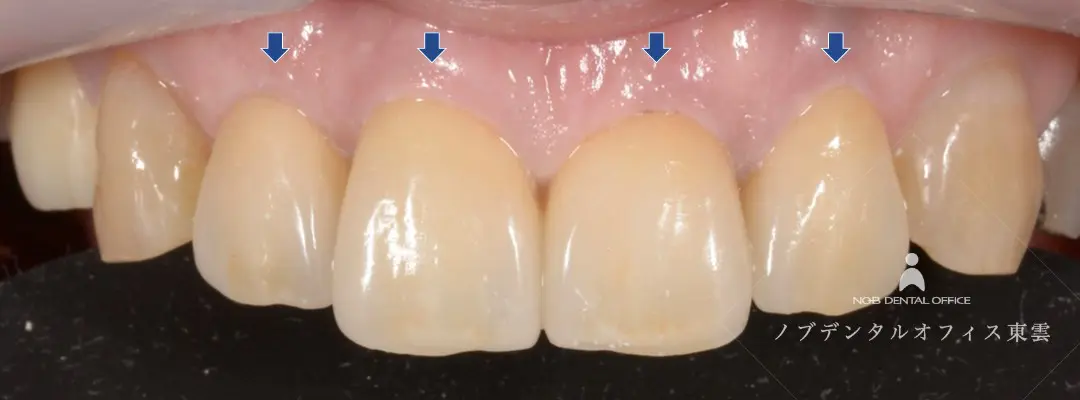

「前歯4本の色が気になる」とご来院された患者様です。

治療前は、前歯の歯ぐきとかぶせ物の間に段差があるため清掃・お手入れが難しく、虫歯や歯周病のリスクが高い状態でした。

また、かぶせ物の土台として入っていたメタルコアにもすき間があるように(左下写真)、歯の奥側にも感染があり、根管治療・土台の治療も行いました。

さらに、前歯の仕上がりをより自然に仕上げるために、歯ぐきの位置をそろえる処置も行いました。